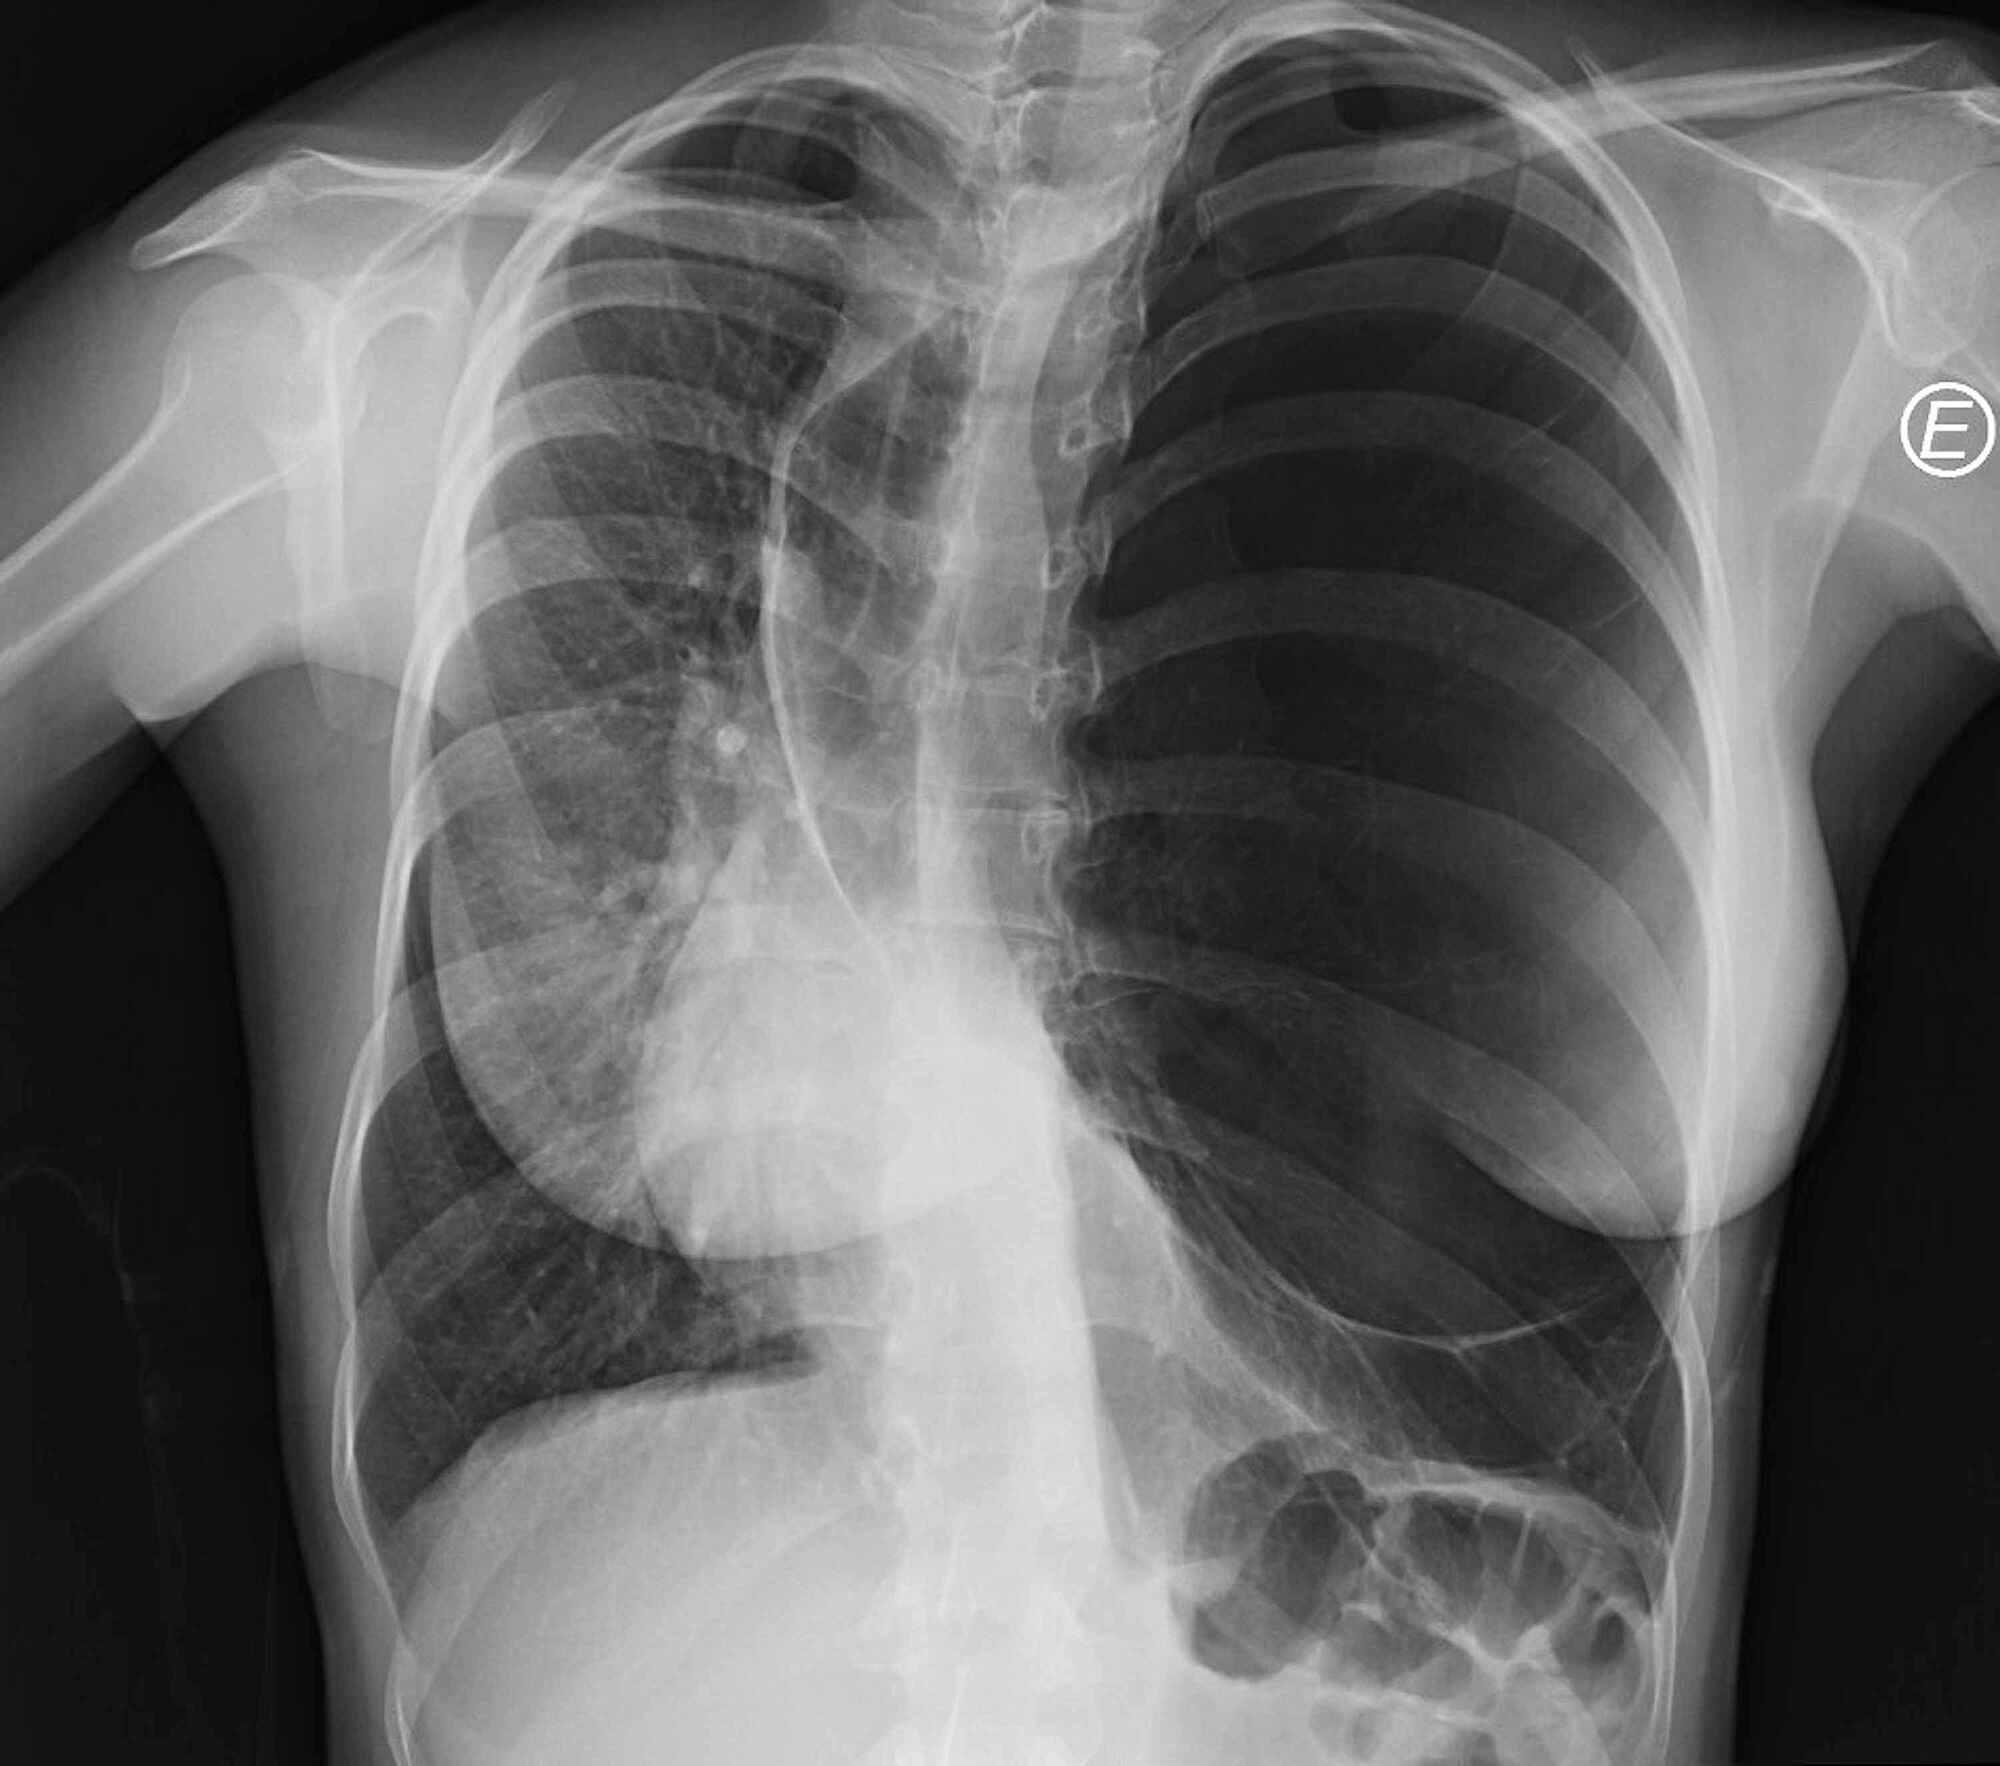

Congenital Lobar Emphysema Chest X Ray . the hrct findings were characteristic of congenital lobar emphysema (cle). congenital lobar emphysema (cle). Radiolucent expanded right lung in a newborn, compatible with congenital lobar emphysema (rml & rul). congenital lobar emphysema is a rare lung malformation, with an estimated incidence of one case per 20. congenital lobar emphysema (cle), also known as congenital alveolar overdistension, is a developmental.

Radiolucent expanded right lung in a newborn, compatible with congenital lobar emphysema (rml & rul). congenital lobar emphysema (cle), also known as congenital alveolar overdistension, is a developmental. congenital lobar emphysema is a rare lung malformation, with an estimated incidence of one case per 20. the hrct findings were characteristic of congenital lobar emphysema (cle). congenital lobar emphysema (cle).

Congenital Lobar Emphysema Chest X Ray congenital lobar emphysema is a rare lung malformation, with an estimated incidence of one case per 20. congenital lobar emphysema is a rare lung malformation, with an estimated incidence of one case per 20. the hrct findings were characteristic of congenital lobar emphysema (cle). congenital lobar emphysema (cle). congenital lobar emphysema (cle), also known as congenital alveolar overdistension, is a developmental. Radiolucent expanded right lung in a newborn, compatible with congenital lobar emphysema (rml & rul).